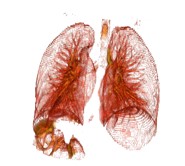

2.5 效果

以下图片是使用3dslicer渲染出来的。